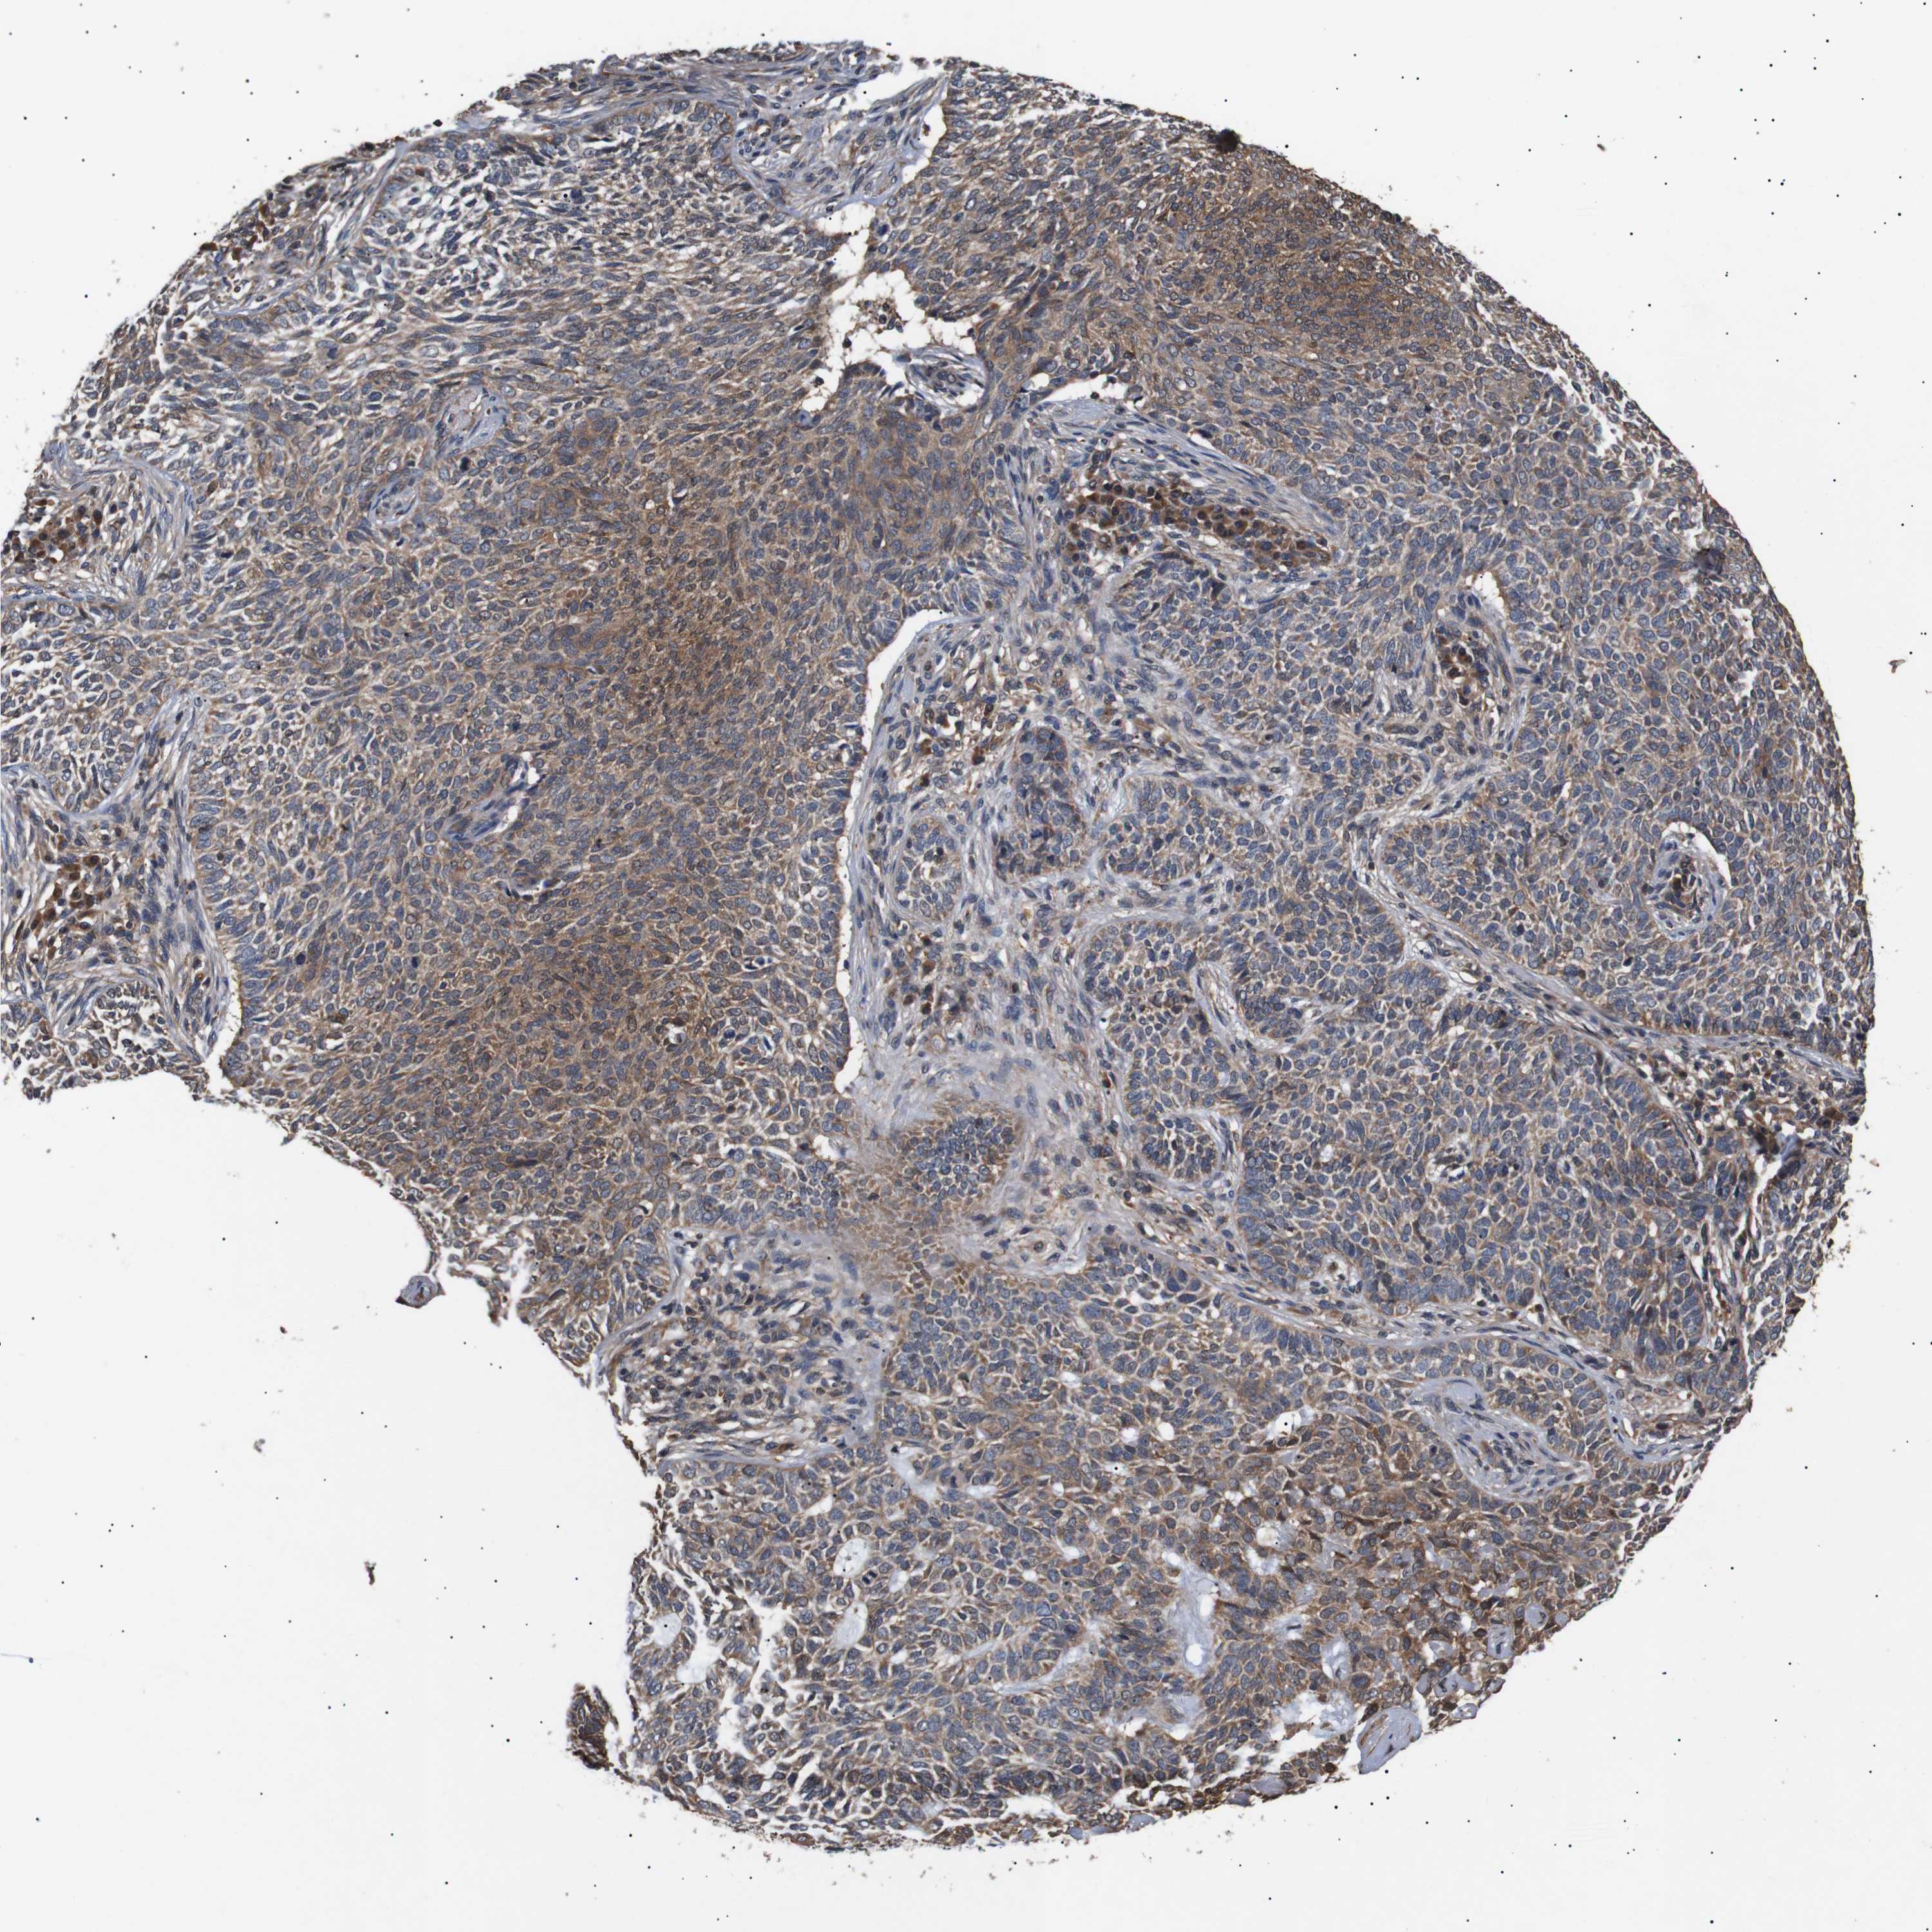

SKIN CANCER - Protein expressioni

A mouse-over function shows sample information and annotation data. Click on an image to view it in a full screen mode. Samples can be filtered based on level of antibody staining by selecting one or several of the following categories: high, medium, low and not detected. The assay and annotation is described here.

Antibody staining in the annotated cell types in the current human tissue is reported as not detected, low, medium, or high, based on conventional immunohistochemistry profiling in selected tissues. This score is based on the combination of the staining intensity and fraction of stained cells.

Each image is clickable and will lead to virtual microscopy that enables deeper exploration of all samples and also displays staining intensity scores, fraction scores and subcellular localization as well as patient and tissue information for each sample.

Antibody CAB025656

Staining

Medium

Basal cell carcinoma